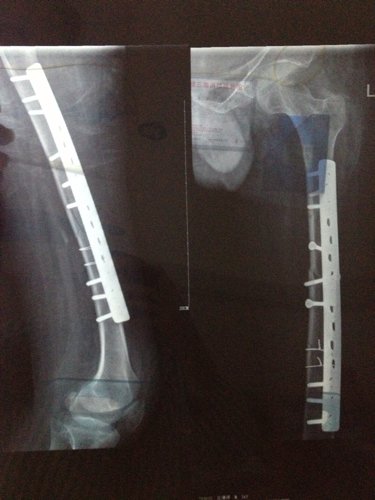

你好医生!左腿原来有小儿麻痹证,就在上个月11号不小心跌倒骨折13号做手术加钢板!现在在家休养 现 你好医生!左腿原来有小儿麻痹证,就在上个月11号不小心跌倒骨折13号做手术加钢板!现在在家休养。现在腰很痛?是怎么回事,有过性生活。现在简单吃两种药?请问医生像我这种情况会不会很难恢复原来那样?是不是还要吃些什么?还有要不要外敷些什么?还要腰很痛怎么办,谢谢! 点击展开 匿名用户 2014-04-08 09:50 为您推荐: 其他回答 病情分析: 你好,考虑是恢复期间的应急反应。 指导意见: 可以多食瘦肉、鱼、鸡蛋、牛奶、豆类食品以及新鲜蔬菜、水果等,注意逐渐恢复锻炼。 独水凡_xjeq 2014-04-08 10:51 相关问题 你好、请问:左小腿骨折做手术取钢板后可以同房吗?同房有影响吗?还是需要等的话要多久? 骨博士你好,我膝盖上面一点点骨折了,已经八个月了能取出钢板了吗 骑电动车把左股骨颈摔骨折了,而且左腿是小儿麻痹,女,年龄五十四岁,在家静养能康复吗?有什么好办法吗

你好医生!左腿原来有小儿麻痹证,就在上个月11号不小心跌倒骨折13号做手术加钢板!现在在家休养。现在腰很痛?是怎么回事,有过性生活。现在简单吃两种药?请问医生像我这种情况会不会很难恢复原来那样?是不是还要吃些什么?还有要不要外敷些什么?还要腰很痛怎么办,谢谢!